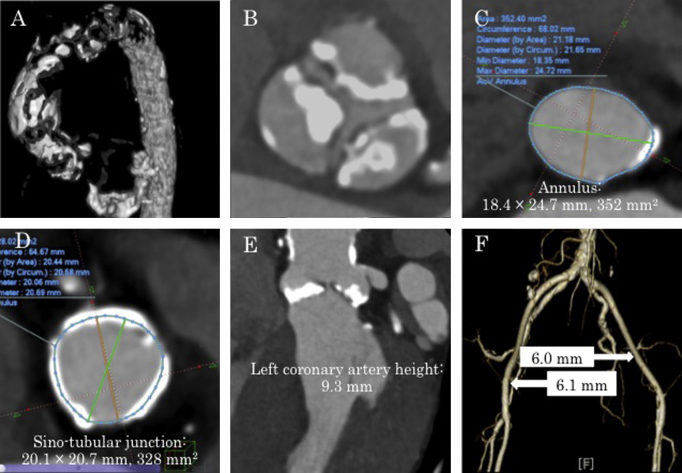

She had a history of hypertension, dyslipidemia, and chronic kidney disease. Her body surface area was only 1.21 m2, but she had maintained daily activities well and her intelligence was normal. Echocardiography and computed tomography (CT) showed severe AS and mild AR due to degenerative changes (aortic valve area by equation of continuity, 0.39 cm2; maximum velocity, 5.4 m/s; mean pressure gradient, 70 mmHg; regurgitant volume, 17 ml; regurgitant fraction, 31%; effective regurgitant orifice area, 0.11 mm2; aortic annulus, 18.4 mm × 24.7 mm, 352 mm2) (Fig. 1, Fig. 2). CT revealed a short distance of 9.3 mm from the aortic annulus to the left coronary artery (Fig. 1E), and severe calcification of all three cusps of the aortic valve (Fig. 1B). The sino-tubular (ST) junction was narrow at 20.1 mm × 20.7 mm (Fig. 1D). The ascending aorta was also severely calcified, with the appearance of porcelain aorta (Fig. 1A). Mean diameter of the right iliac artery was 6.1 mm, and that of left iliac artery was 6.0 mm (Fig. 1F). Our heart team judged that surgical AVR was not indicated for the 95-year-old patient with porcelain aorta, and TAVI was also high risk due to anatomical problems. Eventually, we decided to perform PTAV to palliate her symptoms.

Fig. 1.

Computed tomographic (CT) images. (A) Extremely severe calcification of the ascending aorta (porcelain aorta) is observed. (B) Aortic valve leaflets are severely calcified. (C) Aortic annulus is 18.4 mm × 24.7 mm, 352 mm2. (D) Sino-tubular junction is 20.1 mm × 20.7 mm, 328 mm2. (E) Left coronary artery height is 9.3 mm. (F) Ilio-femoral arteries.